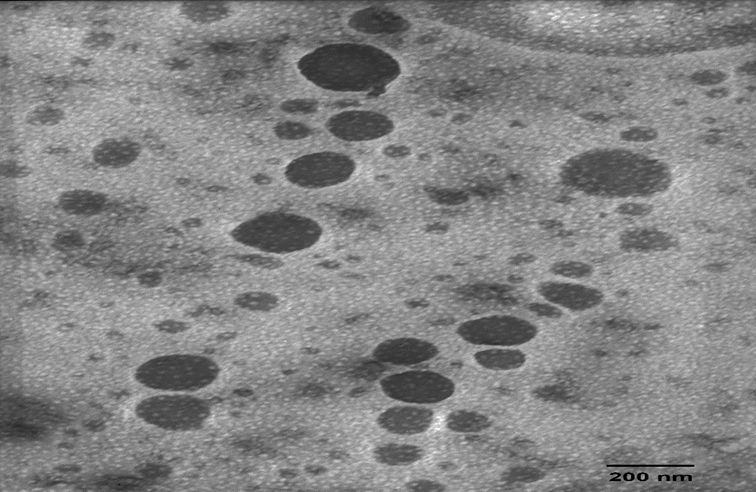

After drying, the nanoparticles F1 had a water content of 9.47% and a yellow color. The results of the morphological evaluation of nanoparticle suspension using TEM and SEM can be seen in fig. 1 and 3, respectively. Polymer-based drug delivery systems takes a chance in many ways for improving the efficacy of active compounds. The biodegradable polymers have the advantage of their metabolites elimination by genuine metabolic processes [12].

Fig. 1: Morphology of the nanoparticle F1 using TEM

Fig. 2: Morphology of the nanoparticle F2 using TEM